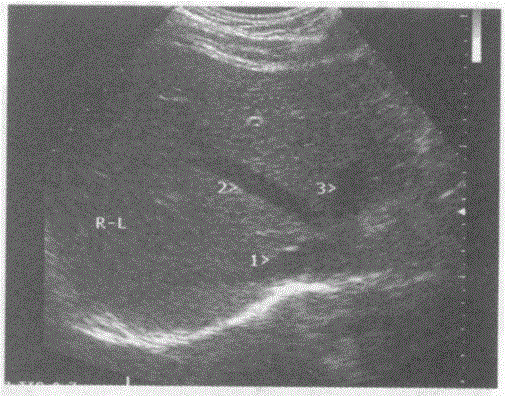

问题 请回答图中1、2、3所指部位的解剖名称:

选项 A.1-肝右静脉、2-肝中静脉、3-肝左静脉 B.1肝左静脉、2-肝中静脉、3-肝右静脉 C.1-门脉右支、2-肝中静脉、3-门脉左支 D.1-门脉右后支、2-门脉右前支、3-门脉左支

答案 A